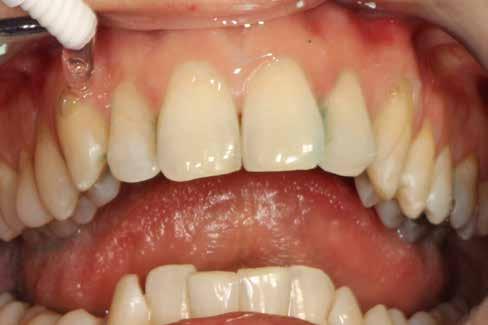

A parodontális elváltozások kezelésének elengedhetetlen része, hogy a páciens a kezelés teljes ideje alatt megfelelően együttműködjön a beavatkozásokat végző fogorvossal, és pontosan kövesse az utasításait. A megfelelő kooperáció elősegítése érdekében javasoljuk, hogy a kezelés minden fázisában egy intraorális szkenner (pl.: Condor; Biotech Dental) segítségével készült, 3 dimenziós modell segítségével ismertessük a páciensünkkel a szájüregi státuszának aktuális állapotát (2. ábra)

Az első találkozás alkalmával a kezelést igénylő terület állapotát egy intraorális szkenner segítségével rögzítjük. Ez a képalkotó eljárás kiegészíti azokat az általánosan alkalmazott vizsgálatokat, mint a radiológiai képalkotás (3. ábra) és a parodontális státuszfelvétel (4. ábra), továbbá hozzájárul a pontos diagnózis felállításához.

A szájüregi státuszról készült digitális 3 dimenziós modell bemutatása, továbbá a látottak részletes megbeszélése révén tudjuk a pácienseinket a leghatékonyabb módon motiválni. A páciensek kooperációját rendkívüli mértékben javítja, hogy ha a kezelési terv egyes lépéseinek megvalósítása után mindig bemutatjuk az aktuálisan elért eredményeinket, és ezáltal számára is jól láthatóvá és jól értelmezhetővé válik a kezelések célja.

A kezelés e szakaszának a befejezésekor a gyulladásos tünetek hiánya, a csökkenő tasakmélység és a szondázást követő vérzés megszűnése megfelelő bizonyítékul szolgálhat az eddig elvégzett beavatkozások hatékonyságára (15. ábra). A páciensek idővel képesek lesznek ennek az állapotnak a fenntartására, ha a fogorvosok által adott instrukcióknak megfelelően végzik a napi szájhigiénés tevékenységüket, és ha ebben megfelelően támogatják őket.

Ebben a fázisban alapvető fontosságú, hogy bemutassuk a páciensnek a kezelés során elért eredményeket, mivel ezzel tudjuk őt leginkább arra motiválni, hogy fenntartsa az elért, megfelelő szájhigiéniás állapotot, továbbá, hogy rendszeresen megjelenjen a jövőben tervezett kontrollvizsgálatokon. A megfelelően kivitelezett LAFMD protokoll befejezésekor, a páciensünk is megfigyelheti, hogy sem gyulladásos tüneteket, sem vérzést nem tapasztal, valamint érezheti a lágyrészek stabilitásából és a megfelelő szájhigiéniás státuszból fakadó előnyöket (16. ábra). A Condor intraorális szkennerel készített színes, háromdimenziós modellek kiválóan alkalmasak a szájüregi státusz bemutatására, továbbá a páciens hatékony motivációjának elősegítésére.